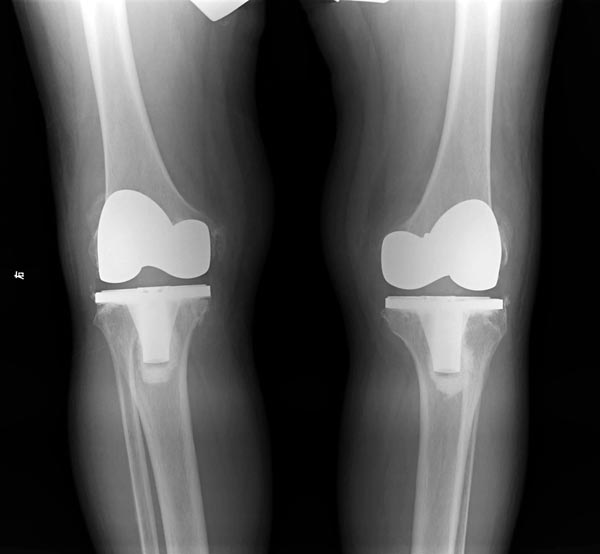

王国照教授亲自主刀进行膝关节关节置换手术

膝关节置换手术获得圆满成功